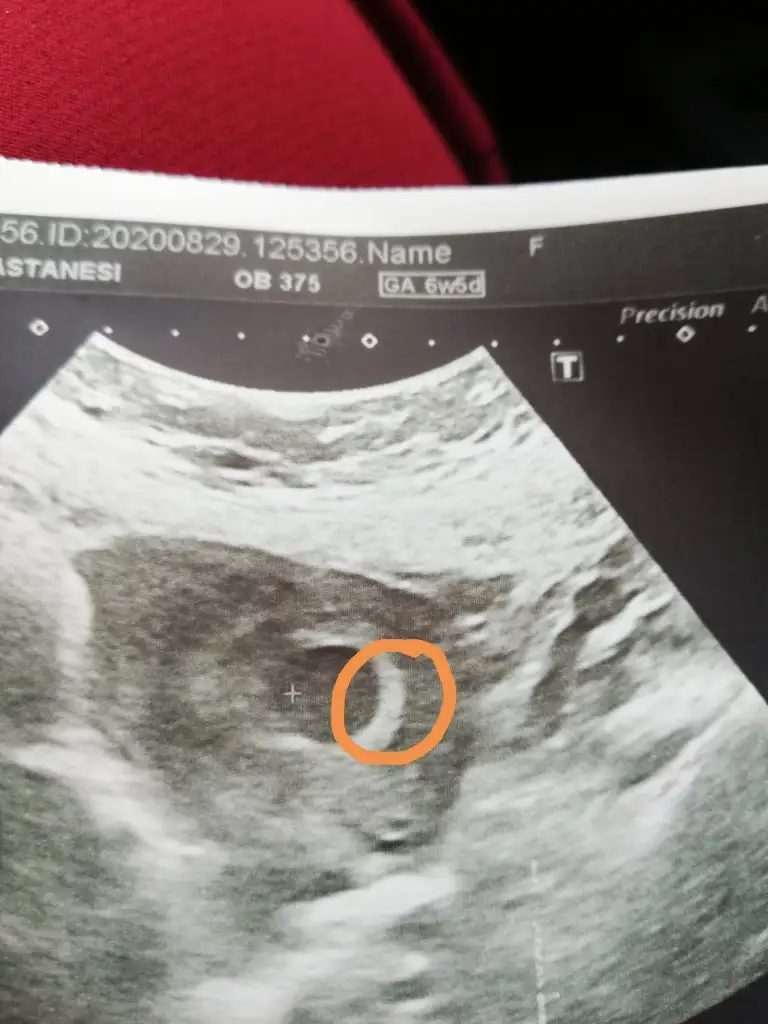

Merhabalar bana da tahmın de bulunabılır mısınız Karın ultrasonumuzu yüklüyorum 6 haftalık

Eklentiler

• DF666934-DC05-4848-BDDB-34210B246E74.webp

DF666934-DC05-4848-BDDB-34210B246E74.webp

17,6 KB · Görüntüleme: 180